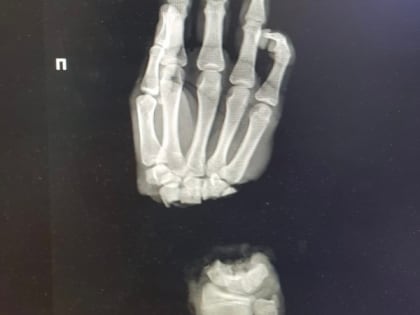

Нижегородские врачи спасли руку 16-летнему подростку

16-летний парень из Владимирской области оказался в нижегородском медучреждении, после того как случайно отрубил себе руку.

Нижегородские медики пришили подростку из Коврова отрубленную руку

Нижегородские медики пришили кисть подростку из Коврова. Юноша поступил в ПИМУ со страшной травмой: он отрубил себе руку, когда колол дрова.

Нижегородские хирурги пришили подростку отрубленную топором кисть

Врачи Университетской клиники ПИМУ пришили подростку отрубленную кисть. Об этом рассказал глава вуза Николай Карякин в соцсетях.